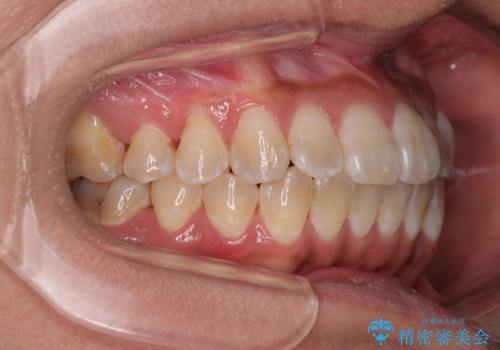

全く目立たないワイヤー矯正 上下裏側矯正

- 上下の前歯のでこぼこを気にして来院された患者様です。

職場の都合により、表側のワイヤー装置や着脱作業が頻繁なマウスピース矯正は困難とのことで、全く目立たない裏側矯正装置を用いて口元を整えることとしました。

途中転勤や出産があり、通院できない期間が長くありましたが、無事に歯列を整えることができました。